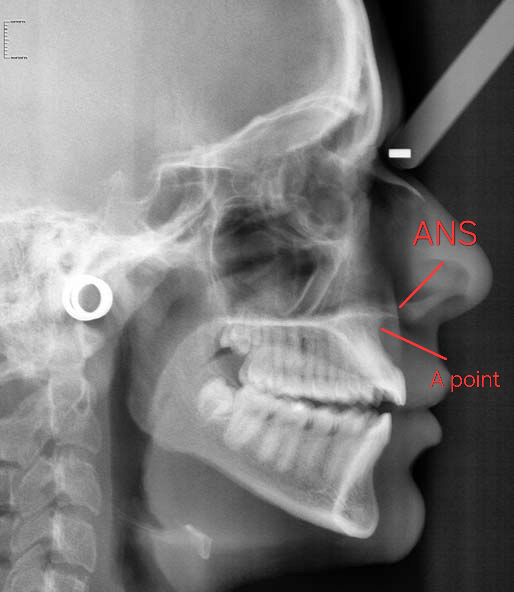

I hypothesise the philtrum curve is due to the relationship between the ANS and the A point of the maxilla (the infradentale can also be part of the problem in people with bimaxillary protrusion but that's for another time).

Here above it is labeled for you plebs.

When the A point moves forward but the ANS doesn't move forward (as much) the result will be a "chimp lip".

But yussimania how can you prove this?

See the difference in relation between the ANS and the A point. It's also evident on the soft tissue part of the scan.

I hypothesise the philtrum curve is due to the relationship between the ANS and the A point of the maxilla (the infradentale can also be part of the problem in people with bimaxillary protrusion but that's for another time).

Here above it is labeled for you plebs.

When the A point moves forward but the ANS doesn't move forward (as much) the result will be a "chimp lip".

But yussimania how can you prove this?

See the difference in relation between the ANS and the A point. It's also evident on the soft tissue part of the scan.